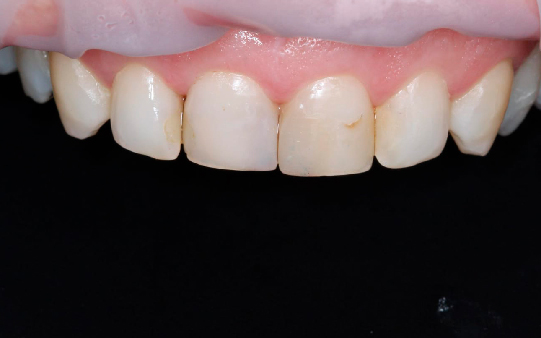

Protocolo em Resina Acrílica: boa estética, acessível, indicado para reabilitações com ótimo custo-benefício.